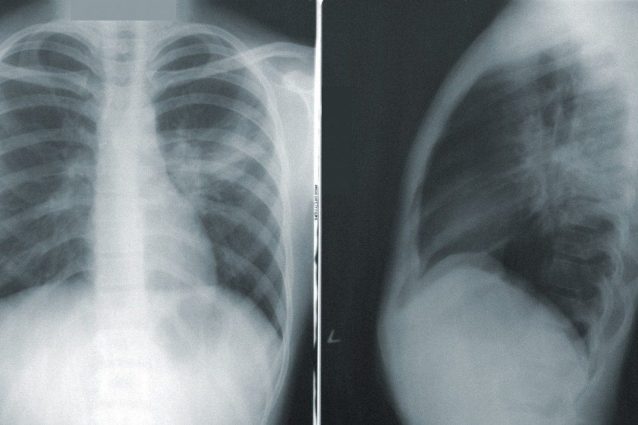

Anche in pazienti asintomatici o con sintomi lievi una radiografia al torace può indirizzare verso una diagnosi di covid-19. Lo ha scoperto un team di ricercatori dell'Irccs Galeazzi e dell'Università Statale di Milano, che ha analizzato il primo focolaio di coronavirus svelato in Italia, quello di Codogno. In 100 lastre su 170 di pazienti della ex "zona rossa" le immagini sono riconducibili a una polmonite interstiziale bilaterale.